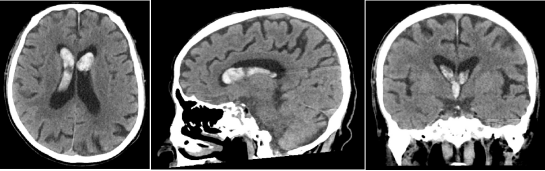

刘爷爷的身体一向硬朗,日常生活基本能够自理,但是20多天前,他开始出现精神萎靡,爱睡觉,大小便失禁的情况,最近更是出现严重的头疼、呕吐,孩子们赶紧把他送到我院急诊神经科,头部CT检查才发现刘爷爷脑室内大量出血,导致脑积水、颅内高压,必须立即手术治疗。

图2 头颅CT提示脑室系统内积血、脑室扩张